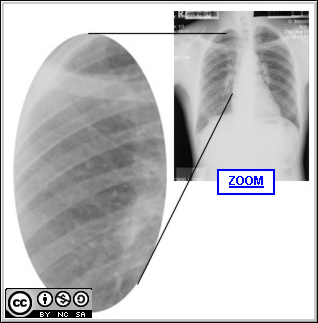

The X-ray and detail above represent a low profusion of simple silicotic nodules.        The X-ray above illustrates a higher profusion of simple, nodular silicosis.

The X-ray on the left is is an example of PMF. The detail shows the typical features of the upper lobe masses (>1 cm) that develop in PMF as the simple nodules aggregate.        Tuberculosis is one of the most important complications of silicosis (also discussed under TB and occupation).